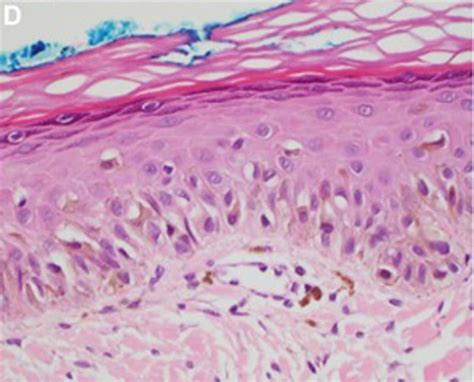

Inicialmente, cuando la proliferación de melanocitos tumorales es aún muy escasa, casi el único dato que nos puede orientar es la distribución irregular de los melanocitos en la capa basal, que se distribuyen en un número discretamente superior al habitual y de forma no equidistante, sobre una dermis con elastosis solar evidente. También puede ayudar la aparición ocasional de filas de melanocitos en la capa basal de la epidermis y la extensión al epitelio folicular de los mismos, cuando están presentes.

Habitualmente en estas fases la atipia aún no es muy llamativa y puede haber un pleomorfismo nuclear discreto. Tras esta fase inicial sutil, aparece una fase con una proliferación de melanocitos mucho más evidente, con frecuentes hileras de melanocitos sustituyendo a los queratinocitos basales, a veces acompañados de grietas de retracción junturales.

Los melanocitos tumorales infiltran también la capa basal del epitelio folicular y no es raro que los melanocitos neoplásicos rebasen el infundíbulo folicular para alcanzar porciones más profundas del folículo, como las glándulas sebáceas o el segmento inferior. Todo ello desarrollado sobre una dermis con elastosis solar, a veces muy evidente, y con un cierto infiltrado linfocitario.

La atipia de melanocitos, cuando está presente, puede ser también de ayuda, a veces con melanocitos epitelioides atípicos, pero otras veces la atipia no es llamativa y los melanocitos son linfocitoides o angulados o fusiformes, pero en casi cualquiera de estas variedades morfológicas los núcleos suelen mostrar algún pleomorfismo, con tamaños y formas diferentes, un grado variable de picnosis nuclear y nucléolos eosinófilos evidentes.

Imagen histológica de un lentigo maligno.

En nuestra experiencia, en esta fase diagnóstica del LM es bastante habitual encontrar nidos junturales de melanocitos atípicos. En estos casos, por desgracia, si no se tienen en cuenta las características clínicas de la lesión, no es raro el diagnóstico histológico de tales lesiones como «nevus junturales con atipia» o «nevus displásicos» o similares.